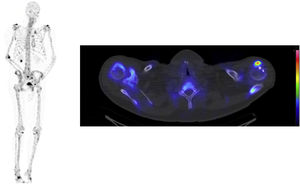

72-year-old male with prostate cancer cT3b, Gleason 7b and PSA level of 23 µg/l. Two weeks after diagnosis, a 99mTc-HDP whole body bone CZT SPECT/CT scan (Fig. 1) and a computed tomography (CT) scan (no image) were performed to investigate metastases, both scans were negative. Radical prostatectomy was performed and confirmed the finding of pT3b, Gleason score 7b with negative margins, but the PSA level after surgery remained elevated at 22 µg/l. A 68Ga-PSMA-11 PET/CT (Fig. 2) and a 99mTc-MIP-1404 CZT SPECT/CT (Fig. 3) scan were performed postoperatively to investigate possible metastasis and both scans reveal hypermetabolic activity in a 9 mm lymph node in the perirectal fat and in the right scapula with obvious clinical suspicion of metastasis. Previous studies have investigated 99mTc-MIP-1404 and conventional SPECT/CT for staging prostate cancer with promising results [1,2]. Furthermore, general-purpose CZT SPECT/CT cameras have shown high sensitivity and might be a good alternative to conventional cameras [3]. In this case, 68Ga-PSMA-11 PET/CT using a GE Discovery D710 (GE Healthcare; Milwaukee, WI, USA) and 99mTc-MIP-1404 CZT SPECT/CT using a CZT Veriton (Spectrum Dynamics, Caesaria, Israel) have shown comparable findings without inferiority with high lesion uptake in the metastatic lesions compared to the background, which raises the question of whether 99mTc-MIP-1404 CZT SPECT/CT could be an alternative to conventional imaging (99mTc-HDP whole body bone scan and CT) and possibly to 68Ga-PSMA-11 PET/CT for prostate cancer staging, emphasizing the need for further studies. To the authors knowledge this the first prostate cancer patient undergoing the combination of 99mTc-MIP-1404 and CZT SPECT/CT in the scientific literature.